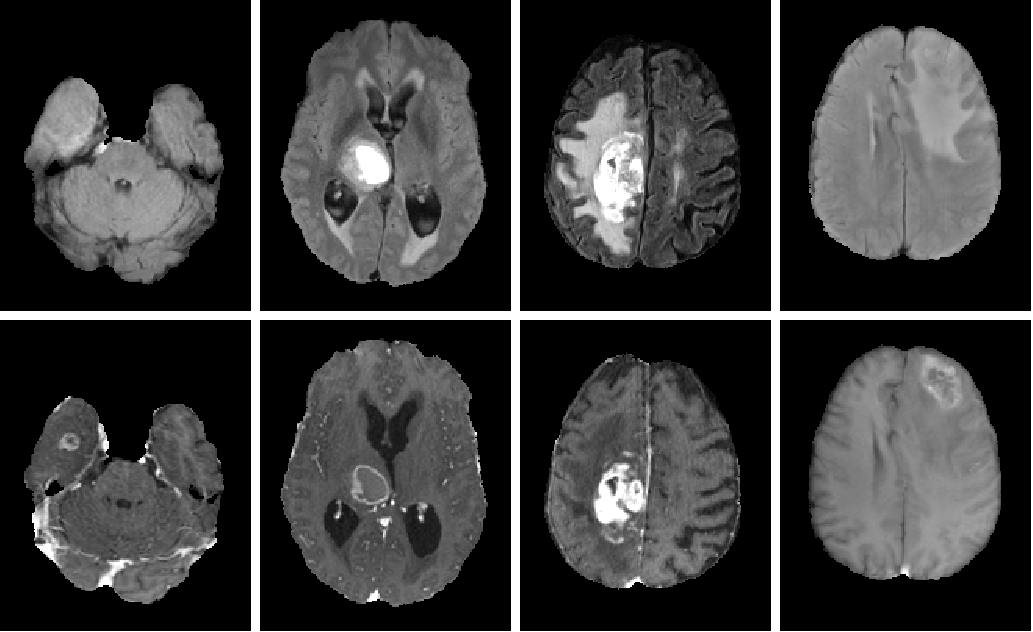

GBM tumor segmentation consists in delineating each region that composes a lesion: necrotic core (NC), enhancing tumor (ET), and vasogenic edema (ED). For that, it is necessary to use MRI sequences that reveal the multiple visual aspects of those regions. For example, FLAIR (T2 fluid-attenuated inversion recovery) activates the edema while T1Gd (post-contrast T1-weighted) activates the enhancing tumor and shows the necrotic core as a non-activated region [22, 6]. Some works show that additional T1 and T2 scans can improve the results, but not significantly compared to FLAIR and T1Gd only [14]. Figure 1 illustrates the different visual aspects of the regions of interest in the FLAIR and T1Gd scans, showing ED, ET, and NC on the left. On the right, it shows that ED can appear with parts saturated and parts with intermediate intensity values. Such differences in appearance may also occur for ET and NC in T1Gd images. Since the selected filter bank of the first layer should activate all relevant regions, the user intervenes by drawing markers in images with such differences and choosing filters from multiple executions of FLIM with different hyperparameters. Other appearance variations in shape, intensity, contrast, and size are presented in Figure 2.

|